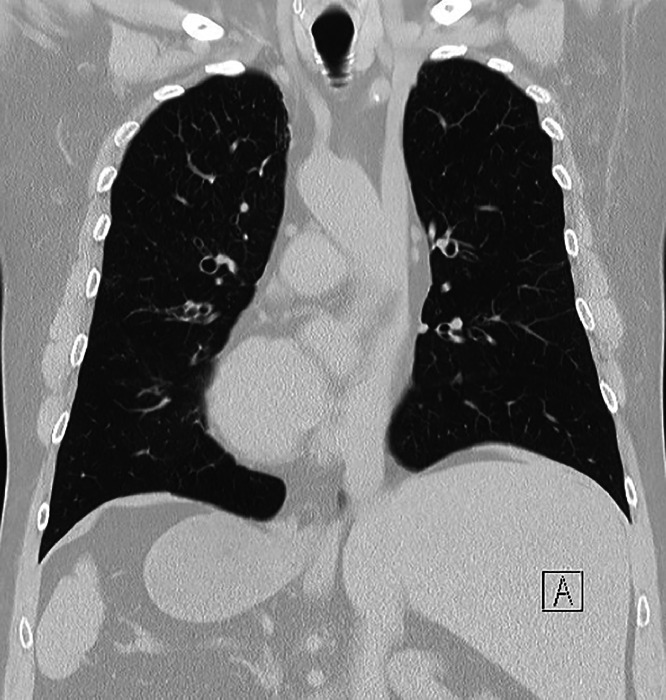

Abstract Image